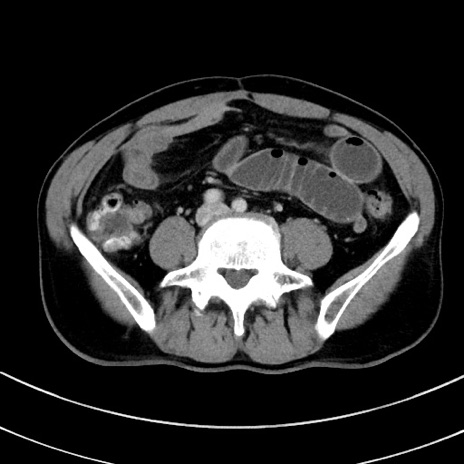

症例8(横断像)

【症例】 60歳代男性

【主訴】 黒色吐物

【現病歴】 4日前から嘔気自覚、2日前の朝食後にも嘔気あり、自分で手で嘔吐反射起こし嘔吐したところ血が混ざっていたため受診。

【既往歴】 5年前汎発性腹膜炎を伴う急性虫垂炎で手術、高血圧、前立腺肥大症、高脂血症

【身体所見】 腹部正中に手術癩痕あり 腹部平坦・軟圧痛なし膨満感あり

【データ】WBC 8400、CRP 4.54